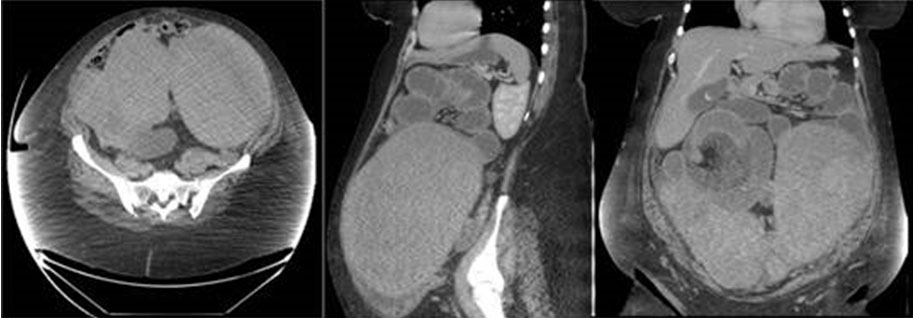

A 42-year-old man presented with a history of progressive left femoral pain radiating to his buttock. He reported worsening symptoms when walking for prolonged periods of time or playing sport. On clinical examination, he had no swelling, no tenderness, nor limitation of movement. Plain radiographs of the left hip showed a lytic lesion containing a central calcification and surrounded by sclerotic margins in the intertrochanteric region of the proximal femur (Figure 1). Axial CT scan reveals intraosseous well defined fat density lesion containing central calcification with sclerotic margins (Figure 2).

Figure 2: Coronal CT scan revealing a well-defined fat density lesion with a central calcification and sclerotic margins.

The CT scan demonstration of intraosseous lipomas consists of a lytic lesion with distinct borders and a negative Hounsfield unit parallel to the adipose tissue. While irregularity of the bone cortex and marginal sclerosis surrounding the lesion are commonly observed [10]. Intraosseous lipoma presents on MRI as a lesion with a high signal intensity lesion on both T1 and T2-weighted images identical to that of adipose tissue that allows differentiation from other bone lesions [10].